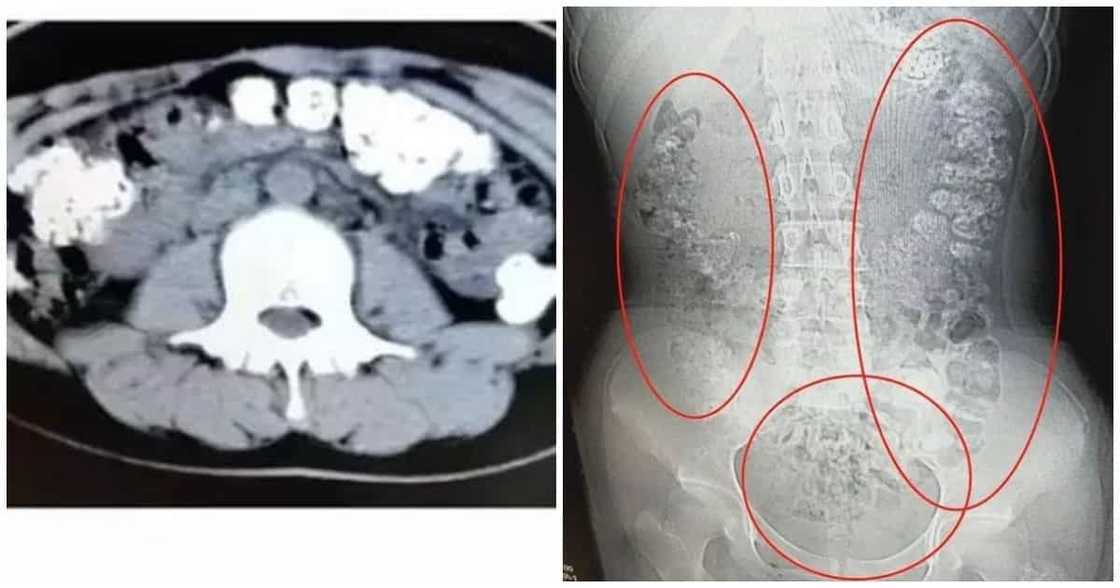

Ayon sa ulat ng The Paper, isang Chinese news site, sa pamamagitan ng CT scan ay nadiskubre ang napakaraming hugis-bilog sa loob ng tiyan ng dalagita.

Sa dami nito ay umabot na ito sa iba pang parte ng katawan niya.

Sa tingin ng mga doktor ay mga 'di natunaw na bubble tea ang mga nakitang hugis-bilog sa loob ng tiyan ni Xiao Shen.